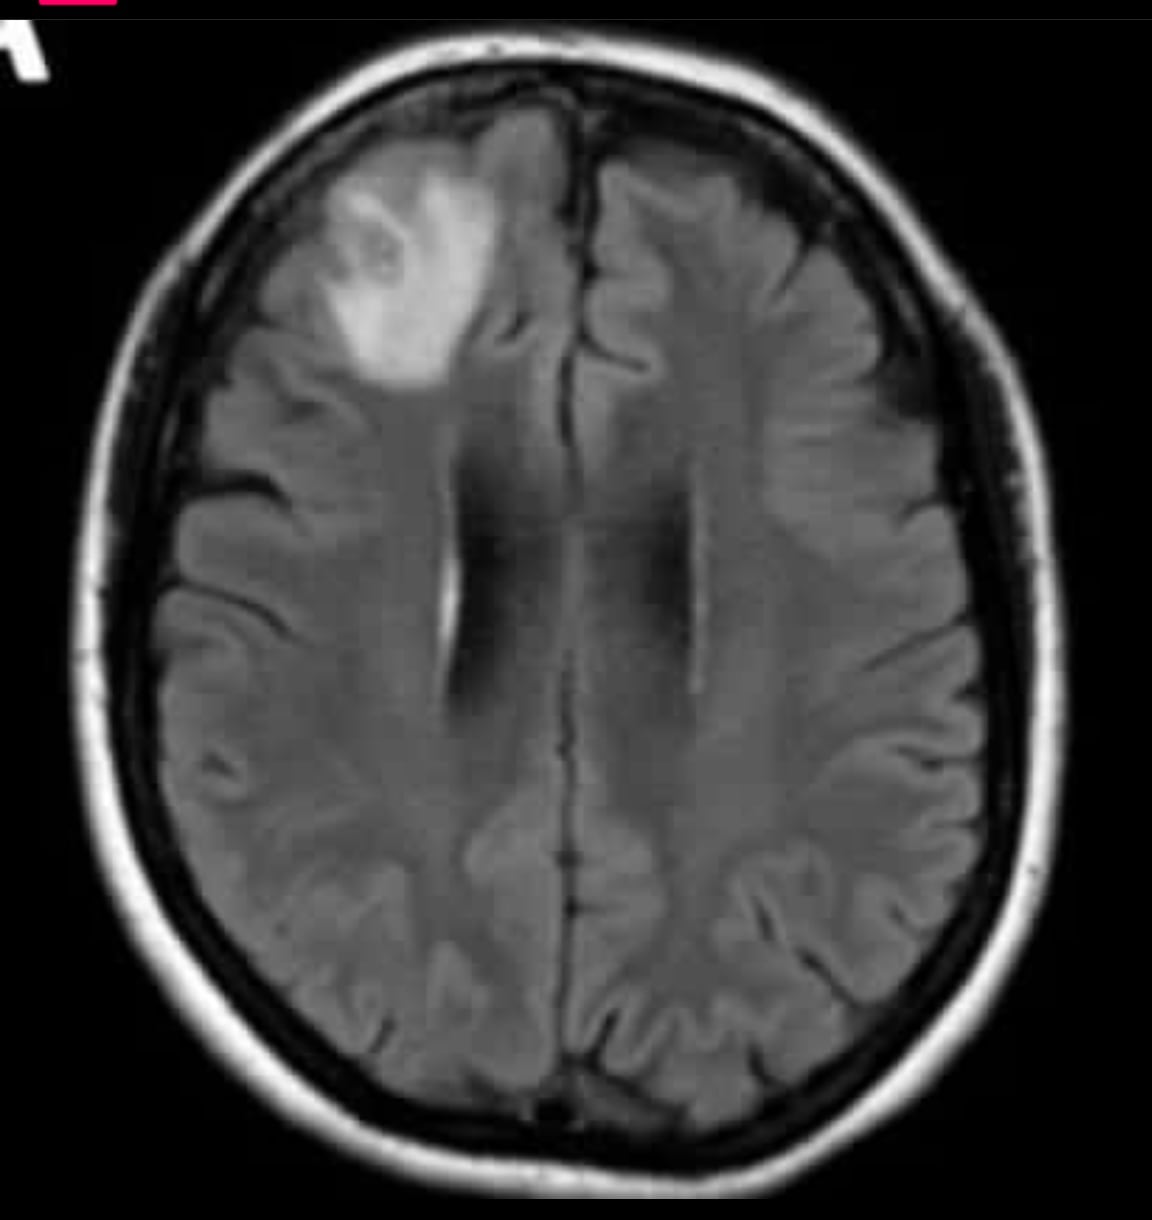

La mujer se sometió a una resonancia magnética el año pasado ya que empezó a experimentar trastornos en la memoria y depresión, dichas imágenes revelaron que la mujer tenía una lesión atípica en el lóbulo frontal derecho.